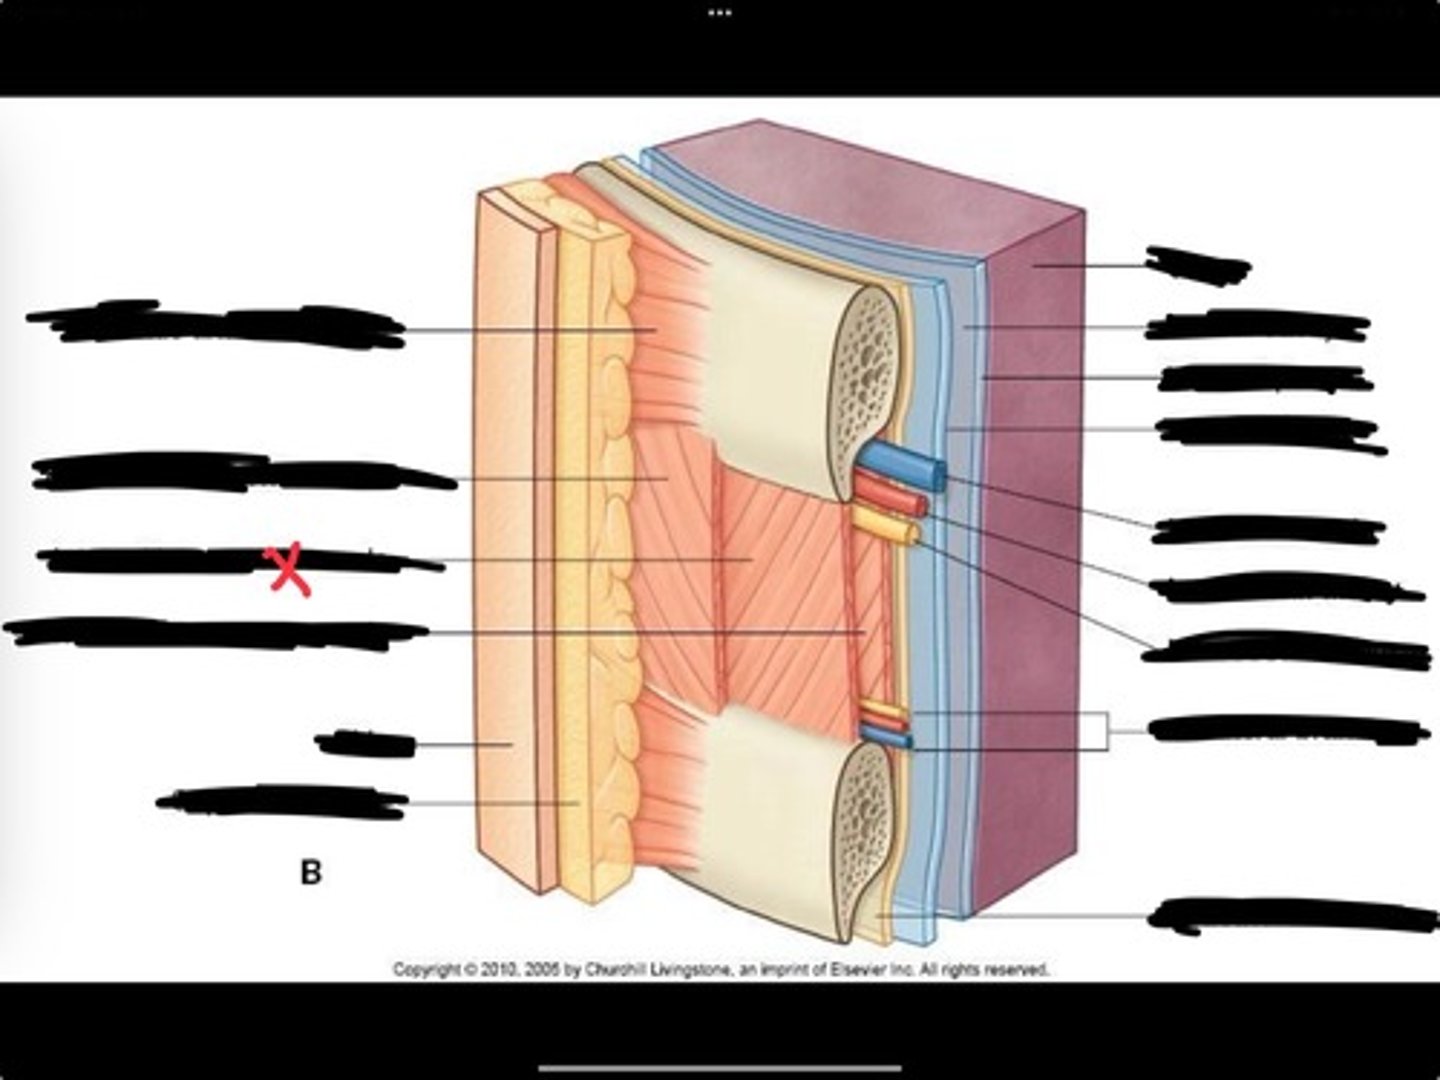

Innermost intercostal muscle

Skin

Internal intercostal muscle

External intercostal muscle

Serratus anterior muscle

Lung

Pleural cavity

Visceral pleura

Parietal cavity

Intercostal vein

Intercostal artery

Collateral branches

Intercostal nerve

Endothoracic fascia